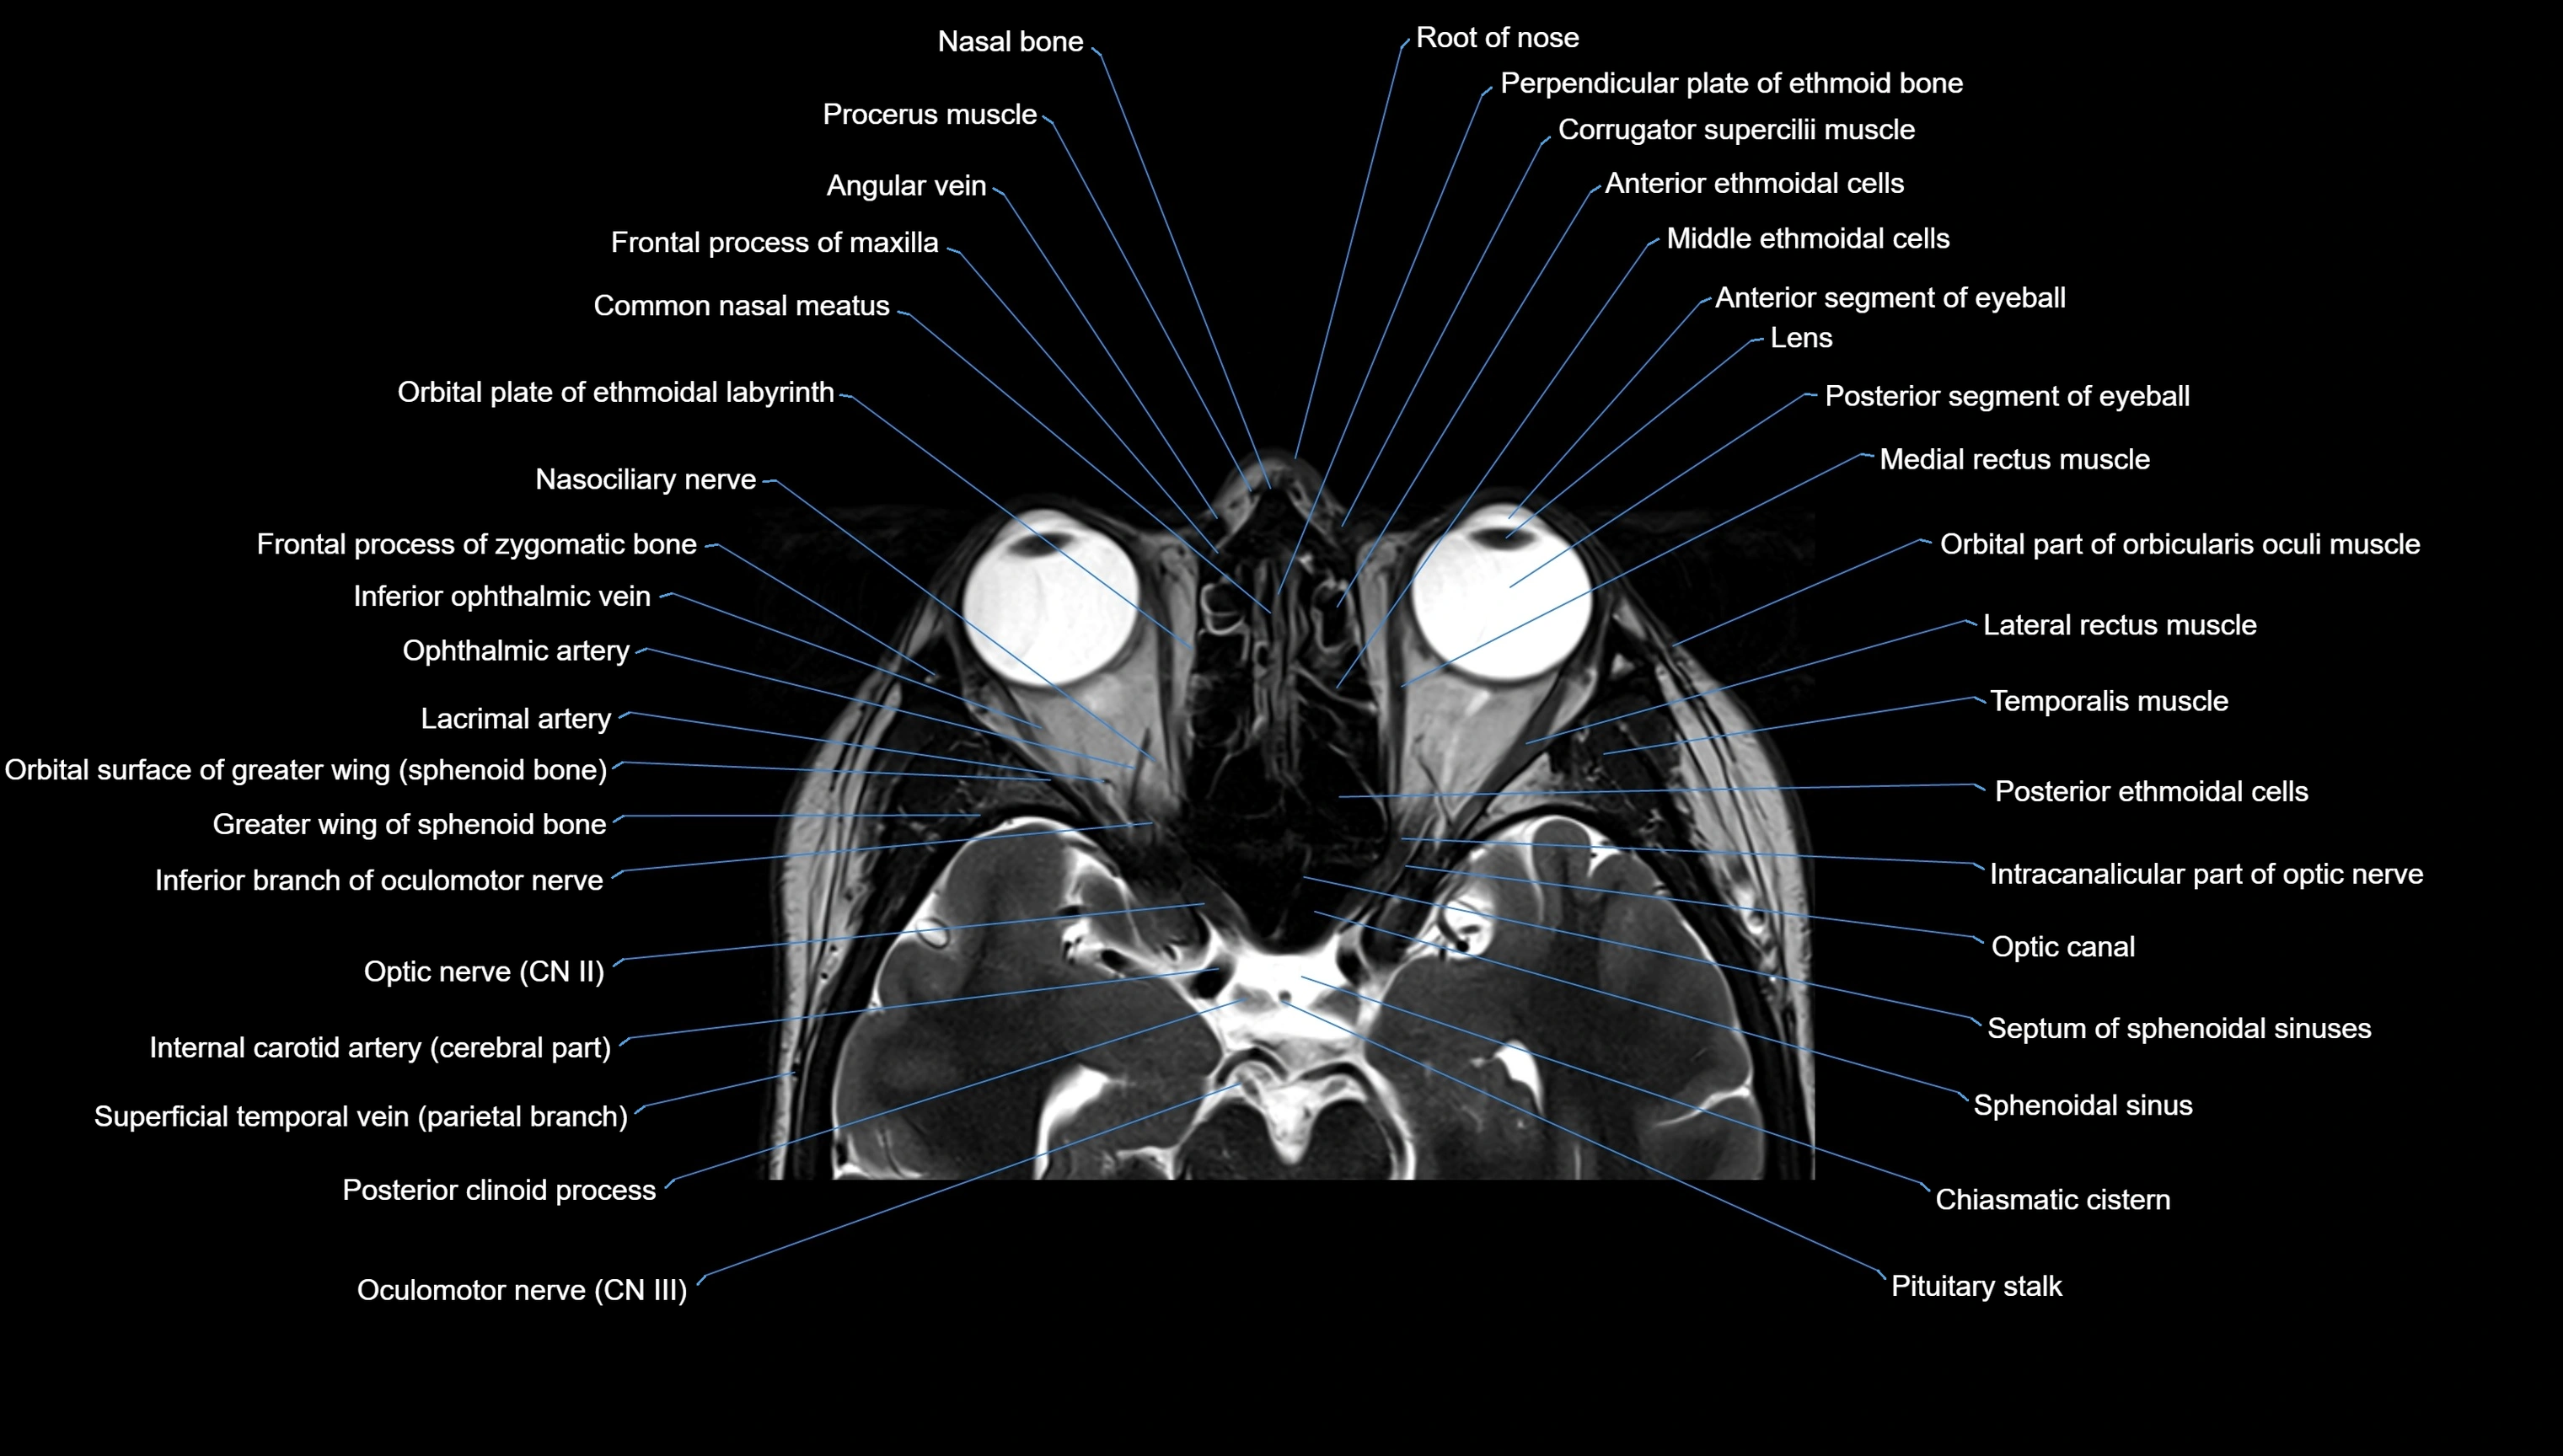

MRI images